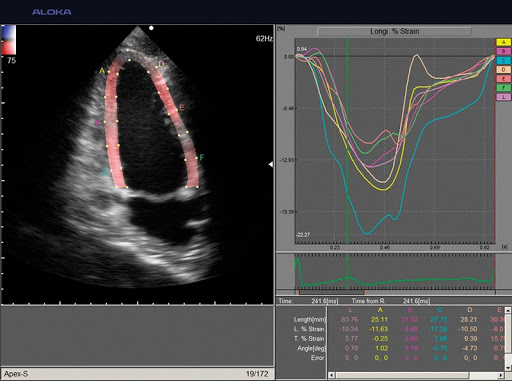

Экспертные функции подойдут для продвинутой диагностики сердечно-сосудистой системы, органов малого таза, вычислений показателей гемодинамики и других узких специализаций. Современные технологии работы с изображениями дают превосходное качество и позволяют извлечь максимум информации. Серошкальная визуализация, допплеровское цветовое картирование кровотока, а также спектральное допплеровское исследование кровотока, которые поддерживает система, позволяют оперативно провести качественные и количественные оценки.

Анализ тканевого допплера (TDI-Strain/Strain Rate)

Экспертная кардиология:

- Strain-анализ

- Недопплеровский анализ ЛЖ